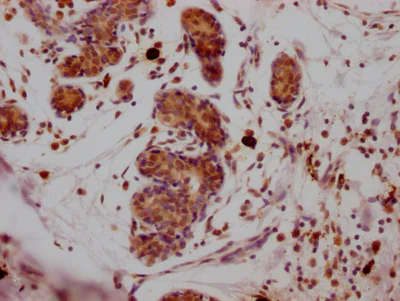

Immunohistochemistry (Formalin/PFA-fixed paraffin-embedded sections) - Anti-SUZ12 antibody [1B10] (AB314166)

Immunohistochemical analysis of ab314166 diluted at 1 : 100 and staining in paraffin-embedded human breast cancer performed on a Leica BondTM system. After dewaxing and hydration, antigen retrieval was mediated by high pressure in a citrate buffer (pH 6.0). Section was blocked with 10% normal goat serum 30min at RT. Then primary antibody (1% BSA) was incubated at 4°C overnight. The primary is detected by a Goat anti-rabbit IgG polymer labeled by HRP and visualized using 0.05% DAB.